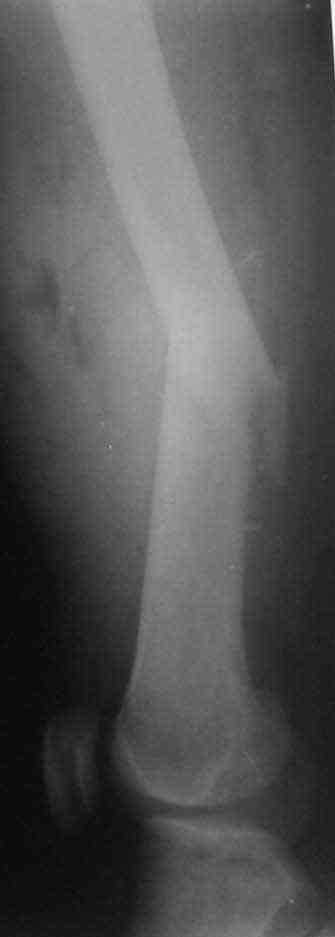

Соматически здоровый 20летний мужчина получил "высокоэнергетическое" ранение левого бедра из автомата Калашникова (5,45 мм).

Сосудисто-нервный пучок не поврежден. Традиционный подход предусматривает радикальную ПХО (расечение, иссечение и т.д.)и применение аппрата внешней фиксации. Хотелось бы услышать мнение коллег: возможен ли в данном случае нетрадиционный подход (лаваж + срочный закрытый интрамедуллярный остеосинтез + VAC) и насколько он обоснован?